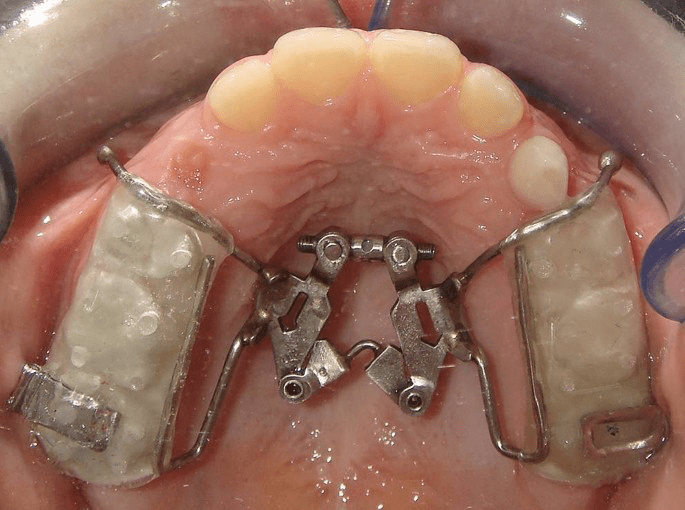

- Protocol: Expands and contracts the maxilla alternately (1 mm/day for a week each, repeated for 7–9 weeks) using a two-hinged rapid maxillary expander.

- Rationale: Mimics the rocking mechanism in tooth extraction, disarticulating circum-maxillary sutures without over-expansion.